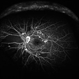

- proliferative diabetic retinopathy (PDR), fibrovascular proliferation, ischaemic diabetic maculopathy

- Fundus photograph of the left eye.